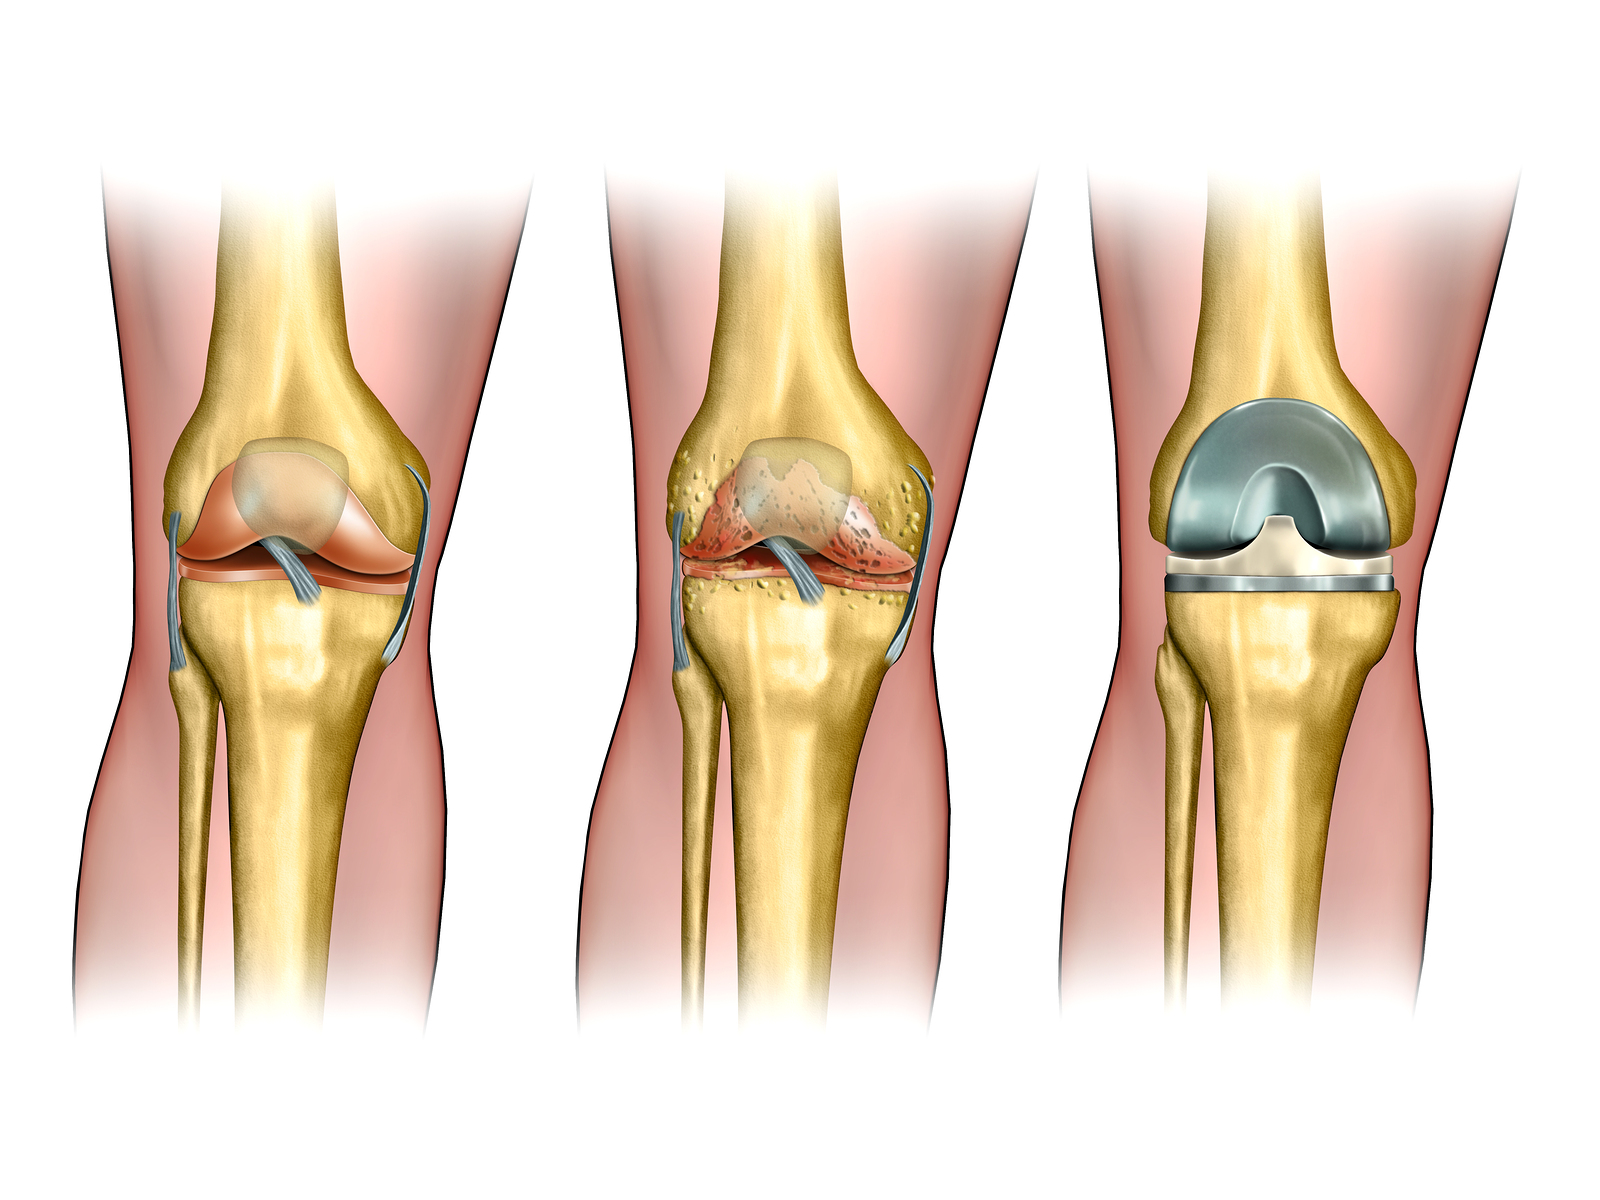

Knee replacement surgery — also known as knee arthroplasty (ARTH-row-plas-tee) — can help relieve pain and restore function in severely diseased knee joints. During knee replacement, a surgeon cuts away damaged bone and cartilage from your thighbone, shinbone and kneecap and replaces it with an artificial joint made of metal alloys, high-grade plastics and polymers.

Knee replacement surgery (arthroplasty) involves replacing a damaged, worn or diseased knee with an artificial joint.

1. total knee replacement (TKR) – both sides of your knee joint are replaced

2. partial (half) knee replacement (PKR) – only one side of your joint is replaced in a smaller operation with a shorter hospital stay and recovery period